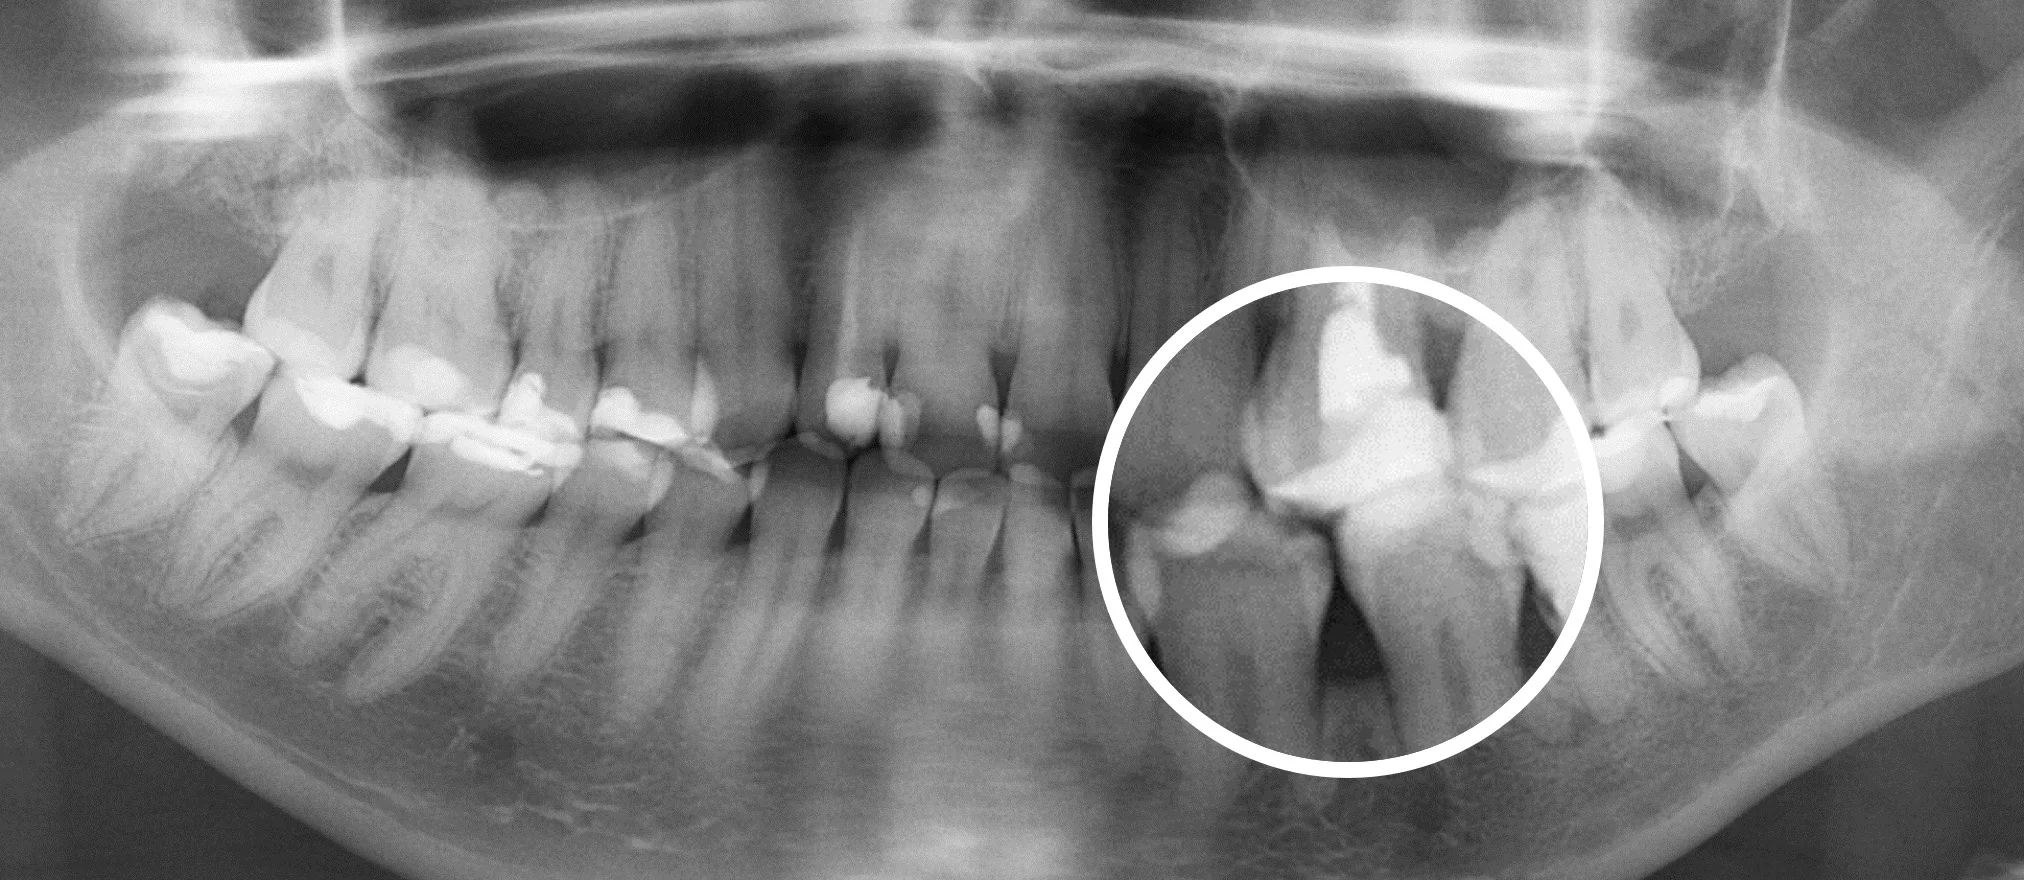

Еще 10 лет назад для того, чтобы провести диагностику зубов стоматологи использовали прицельные R-снимки и ОПГ снимки. Это снимки, которые делаются в 2D формате. Единственное, что врач мог делать с данным снимком, это приближать и удалять изображение.

На смену 2D снимкам пришли КТ снимки (компьютерная томография], которые в обиходе называют 3D снимками —новый уровень диагностики.

3D снимки позволяют стоматологам рассмотреть зубы под разными углами.

Врач изучает 3D снимки на компьютере и в отличии от 2D снимков, он может крутить изображение под любым углом, который ему необходим, заглядывать «внутрь» каждого зуба.

Сравнение 2D и 3D снимков

3D снимки — это новый уровень диагностики. Но при их появлении возникла достаточно большая сложность.

Дело в том, что 3D снимки гораздо более информативны, чем 2D снимки, но на их чтение требуется гораздо больше времени и более высокая квалификация стоматолога, это гораздо более трудоемкий процесс.

Далеко не каждый стоматолог, умеет правильно читать КТ снимки, для этого требуется отдельное обучение. Также стоматологам не хватало времени выделяемого на прием, чтобы проанализировать каждый зуб.

Что привело к тому, что комплексность диагностики начала страдать. Врачи успевали проанализировать только 1-2 зуба за прием.